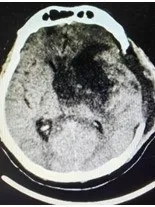

▲ 左图入院CT;右图颅骨修补及脑室分流术后复查CT